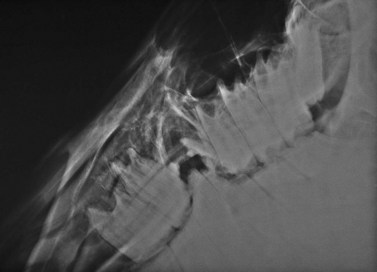

After the apex of a diseased cheek tooth has been exposed using techniques described above, the tooth is repulsed into the oral cavity by striking a dental punch applied to the apex of the tooth and aligned in the direction of the tooth’s path of eruption. Confirming the position of the punch radiographically ensures that the punch is properly aligned (Fig. 20.48). Failure to align the punch correctly may result in damage to a neighboring tooth, the palatine bone, if the tooth is maxillary, or to the internal or external lamina of the mandible, if the tooth is mandibular. When the punch is aligned obliquely to the long axis of the tooth, more force is required to repulse the tooth because the periodontium is not disrupted as efficiently as when the punch is properly aligned. The extra force required is more likely to result in bony or dental sequestra. Because the reserve crowns of the cheek teeth curve axially in a coronal to apical direction, and because the mandibular and infraorbital nerves lie slightly medial to the center of the teeth, applying the punch slightly lateral to the central axis of the tooth reduces the risk of damaging these nerves.

image

Fig. 20.48 When repulsing a tooth into the oral cavity, the punch should be aligned in the direction of the tooth’s path of eruption. Confirming the position of the punch radiographically ensures that the punch is properly aligned. The punch seen in this radiographic projection is in close alignment with the longitudinal axis of the tooth.